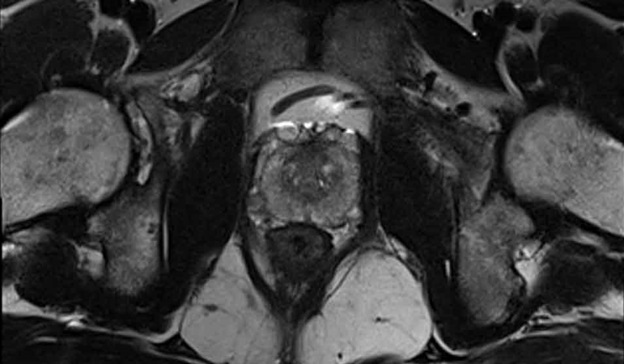

Salvage focal therapy for radiorecurrent prostate cancer has comparable 10-year cancer-specific survival to radical prostatectomy, but fewer complications in matched analyses